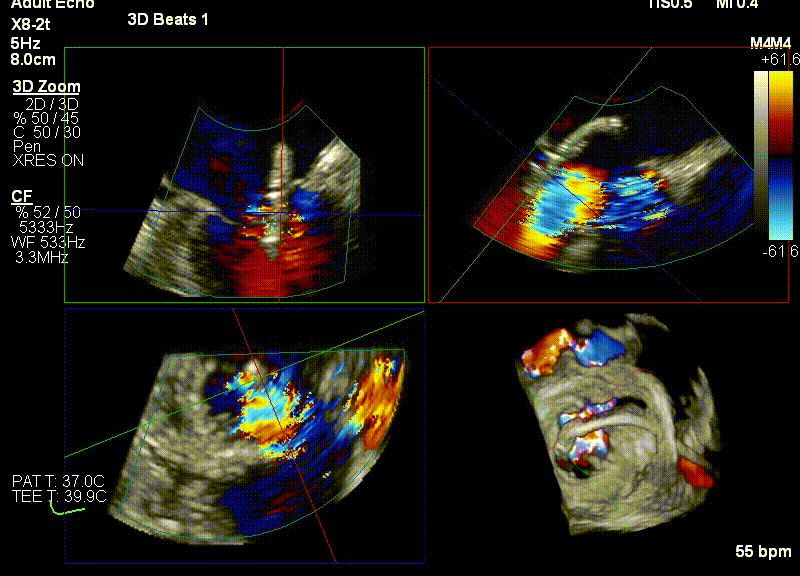

经食道超声引导后,王建安教授将二尖瓣夹NTR夹取C1区瓣叶,准确成功捕获C1前叶和后叶反流最严重区域,并予夹合。使二尖瓣在收缩期由大的单孔变成一大一小的双孔,显著减少了二尖瓣反流。

王建安教授与直播在线专家充分沟通讨论手术方案,为了进一步优化手术结果,计划打开二尖瓣夹后倒置夹臂再回拉至左心房,再次优化二尖瓣夹方向及位置后,多次反复尝试捕捞并夹持瓣叶。

反复测试二尖瓣夹的稳定性,食道超声复查提示二尖瓣夹C1区反流有效改善,术后反流量由术前的4+变为术后的<1,遂精准释放二尖瓣夹。